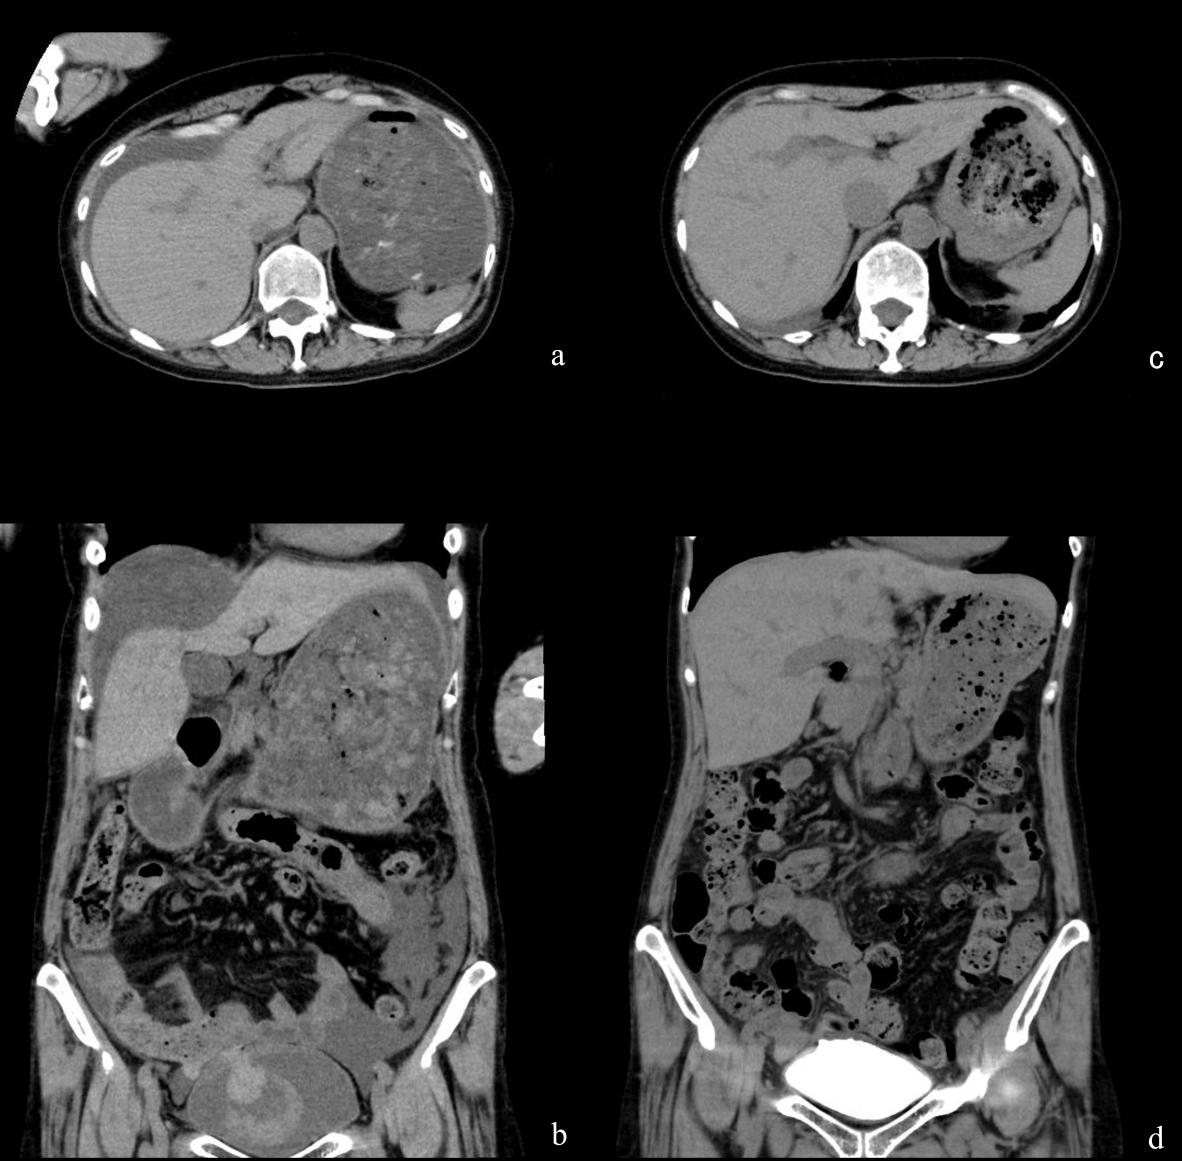

A 58-year-old woman fell on the way home after drinking alcohol for 5 h, and presented to the emergency room (ER) with lower abdominal pain and urinary retention. On examination, she was afebrile (35.0 °C), with a blood pressure of 96/68 mm Hg and a pulse rate of 52 beats per minute (BPM). Oxygen saturation was 94% in room air. Laboratory tests revealed a white blood cell (WBC) count of 14,940/mm3, hemoglobin 13.2 g/dL, serum C-reactive protein (CRP) 0.05 mg/dL, blood urea nitrogen (BUN) 30.0 mg/dL, serum creatinine 1.88 mg/dL, and gross hematuria. Non-contrast abdominopelvic computed tomography (CT) revealed a large amount of ascites (Fig. 1a) and fresh blood clots in an intra-distended bladder (Fig. 1b). Based on these findings, she was diagnosed with post-renal renal failure due to urinary retention, bladder tamponade due to bladder cancer hemorrhage, and ascites due to cancerous peritonitis.

![]() Click for large image | Figure 1. Findings from CT. (a) Non-contrast CT at the upper abdominal level showed a large amount of ascites at admission. (b) Non-contrast CT with coronal reconstruction at the urinary bladder level showed fresh blood clots in the bladder at admission. (c) Non-contrast CT at the upper abdominal level showed a small amount of ascites at 4 days after admission. (d) A CT cystogram with coronal reconstruction at the urinary bladder level showed no extravasation of contrast agent from the bladder dome at 14 days after admission. |

Three days after admission, cystoscopy revealed a small perforation on the right side of the bladder dome (Fig. 2a). The patient was diagnosed with intraperitoneal bladder rupture, and a renal pelvic balloon catheter was placed after cystoscopy. Four days after admission, a second non-contrast CT scan detected loss of fluid in the abdominal cavity (Fig. 1c). Five days after admission, a cystogram showed extravasation of contrast agent from the bladder dome (Fig. 3). Conservative management was continued because urine could be constantly drained and her general condition and laboratory data had improved.

Eleven days after admission, cystoscopy showed no perforation at the bladder dome (Fig. 2b), but a papillary tumor was found on the left side of the perforation scar (Fig. 2c). We performed a cold punch biopsy because cytology findings indicated a class IIIb tumor. The pathological findings showed papillary cystitis. Fourteen days after admission, a third CT cystogram showed no extravasation of contrast agent (Fig. 1d). The patient was discharged in good condition because she could urinate after urethral catheter removal. Eleven days after discharge, cystoscopy revealed no perforation or papillary tumor (Fig. 2d), indicating that the bladder rupture had healed under conservative non-operative management.